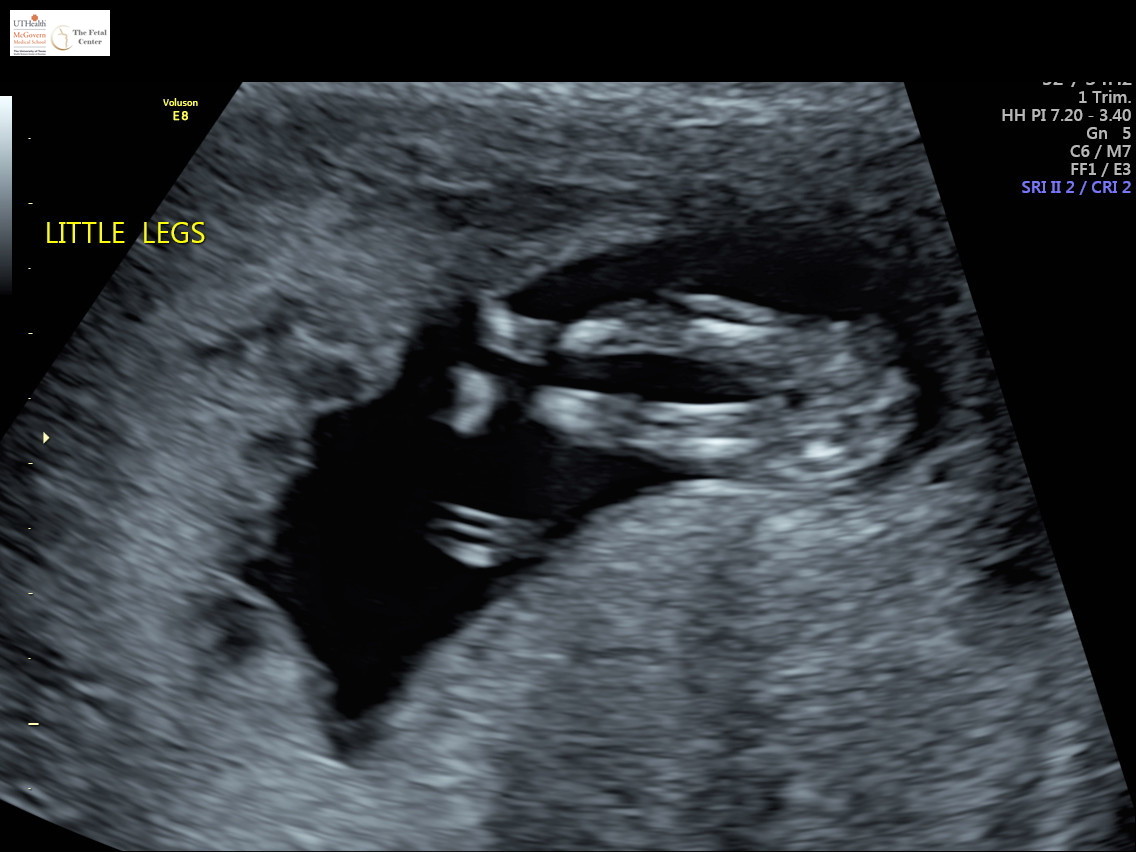

Well, my panorama test said girl but after 5 boys I'm still in disbelief. This ultrasound picture is from 12w4d. I'm now 16w3d but dont have my 20 week scan until July. I would just appreciate if any of you all would weigh in? Thanks so much!!Attachment 41669Attachment 41670